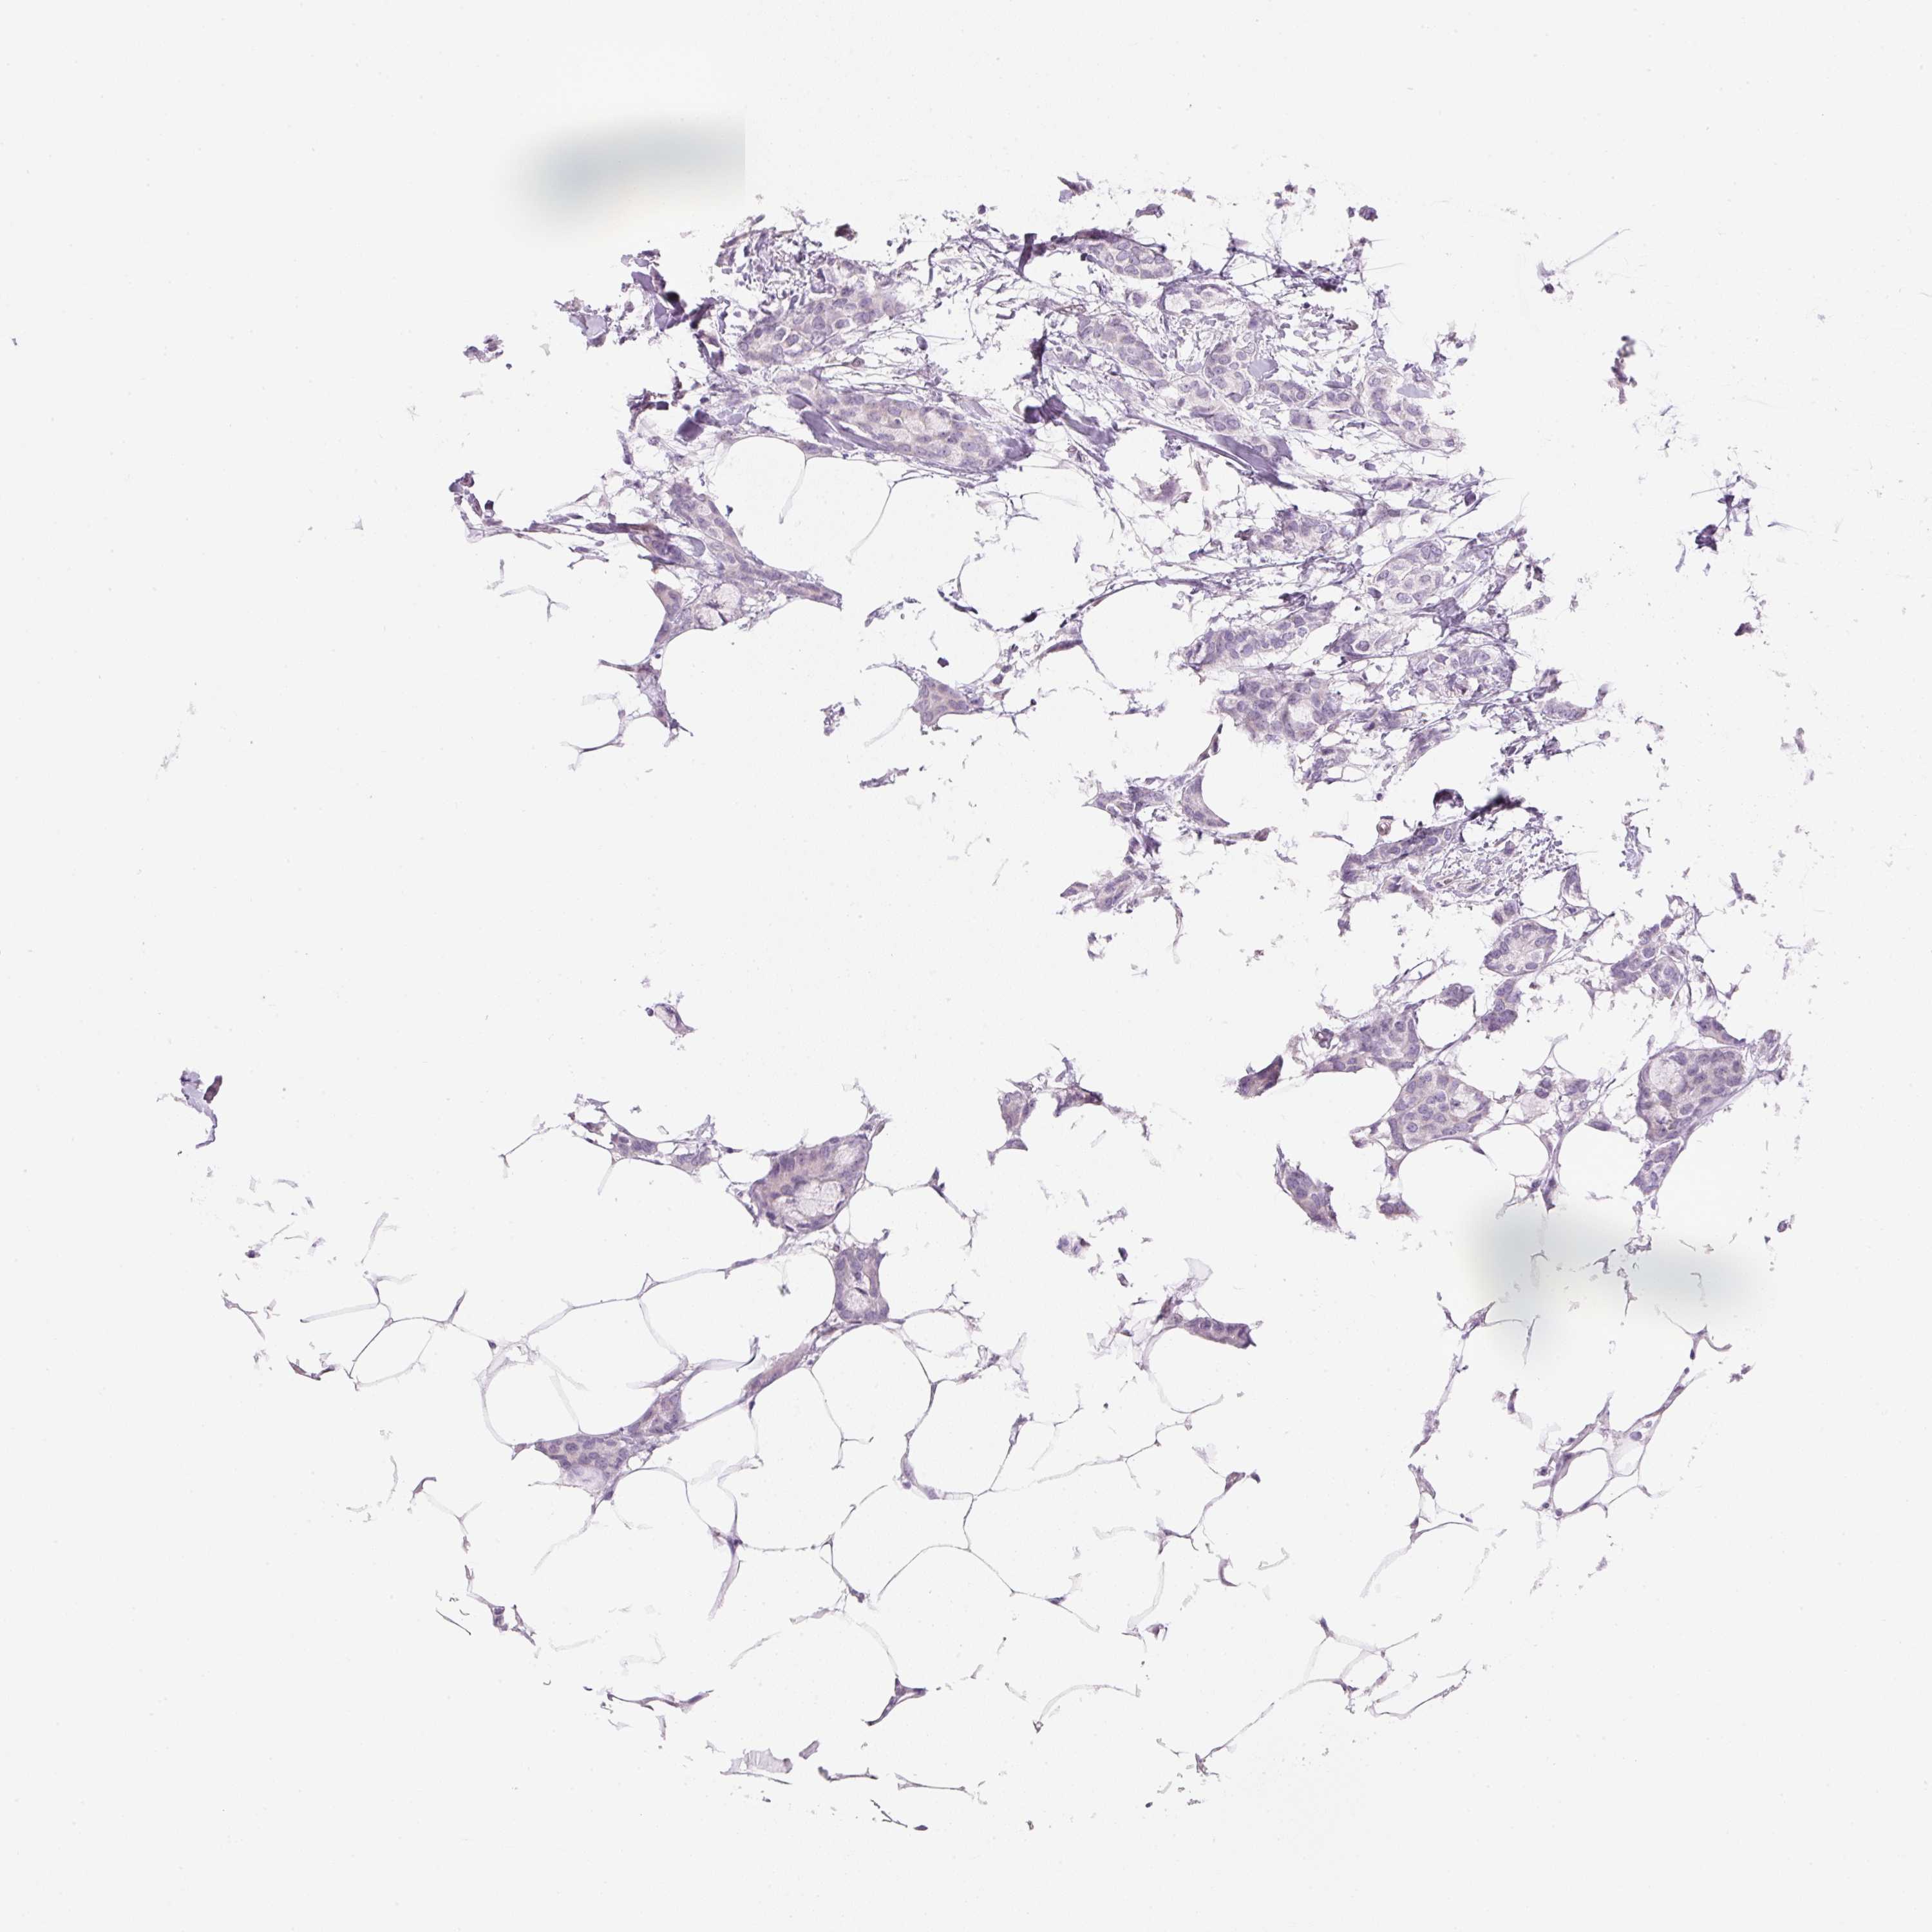

Breast cancer

Human cancer

CANCER BREAST CANCER Show tissue menu